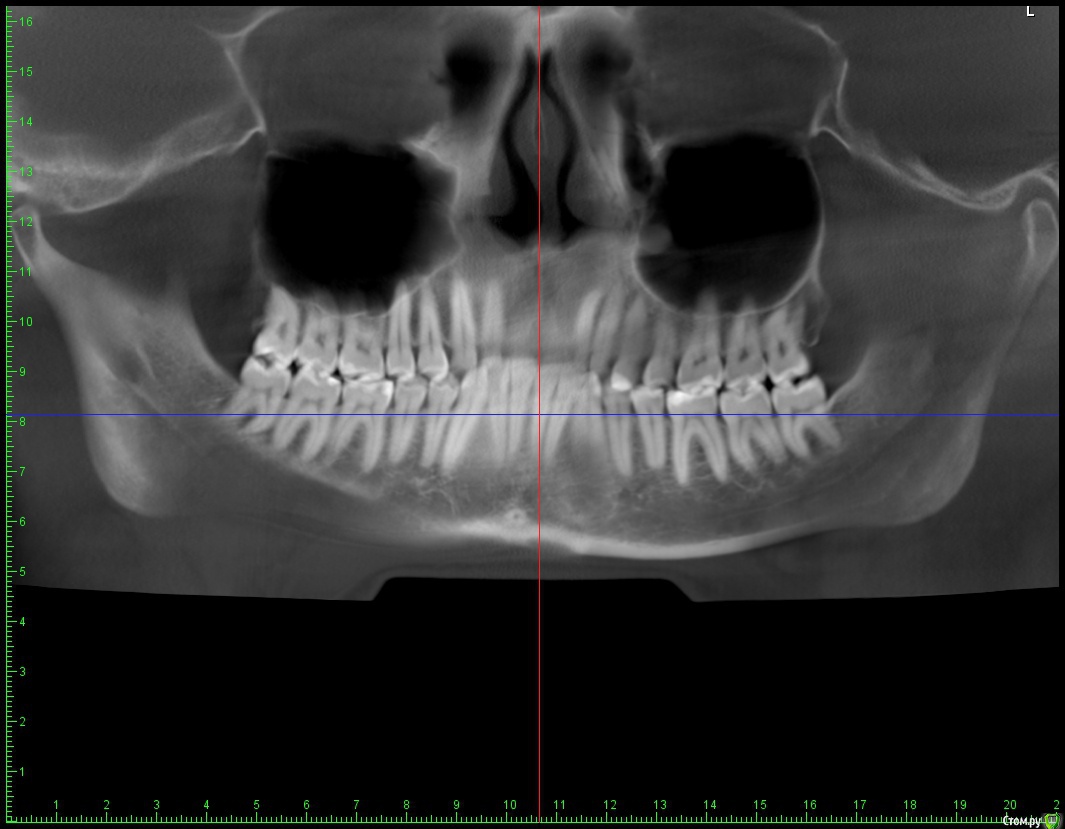

Беспокоит: Возраст 30 лет.  с 15 лет щелчки в суставе, полгода назад появилась периодическая боль - в области сустава, напряжение в жевательных мышцах, в шее  (с шеей вообще давние проблемы - не знаю, что первопричина болей), боли в затылке, голове. Глубокий прикус. Решил прикус исправлять в надежде, что боли уменьшатся.  На снимках видно, что челюсть нижняя заблокирована в заднем положении, мешают верхние резцы, головка сустава смещена

Все мои исследования есть на гугл диске    - там и снимки, и фото, так же результаты КТ и МРТ в электронном виде.

Часть из этого прикрепляю сюда. Ниже - заключение МРТ

Частичное переднее смещение суставного диска ВНЧС справа в положении с закрытым ртом, полная репозиция диска в положении с открытым ртом. Частичное переднее смещение наружного отдела суставного диска ВНЧС слева в положении с закрытым ртом (за счёт внутренней ротации диска), полная репозиция диска в положении с открытым ртом. Остеоартроз ВНЧС справа 1 ст.